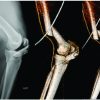

Typical clinical findings on physical examination suggested anterior and posterior ankle impingement syndromes as most likely causes of patient’s symptoms, indicating further radiological investigations. Standard anteroposterior (AP) and lateral (LL) radiographs (Fig. 1) showed diffuse swelling of the ankle and osteophytes of the anterior distal tibia and dorsal talar neck. Os trigonum and unexpected soft-tissue mass were detected in the posterior ankle recess, behind the posterior process of the talus. Magnetic resonance imaging (MRI) of the ankle was performed to evaluate the soft-tissue mass (Fig. 2). MRI demonstrated a nodular lobulated soft-tissue mass in the posterior ankle recess measuring 29 × 18 × 19 mm. T1- and T2-weighted images showed heterogeneous mass, with predominantly low-to-intermediate signal intensity. PD-weighted images revealed a high signal intensity halo surrounding the low intensity signal mass. Furthermore, an additional bone fragment, which was not visible on standard AP and LL radiographs was detected on MRI. It was impinged between distal portion of tibia and fibula. Multislice computed tomography of the ankle was also performed to define the morphology of the bony lesions and help more accurate planning of surgical procedure. The patient’s history, clinical, and radiological findings helped to confirm the diagnosis of anterior and posterior ankle impingement syndromes with the presence of a loose body, impinged between tibia and fibula. Because of typical MRI findings for LPVNS, an excisional biopsy of the soft-tissue mass in the posterior ankle recess was indicated to confirm the diagnosis. Due to concurrent presence of anterior and posterior ankle pathology, we decided to use combined two-portal endoscopic hindfoot approach and anterior ankle arthroscopy within the same operative session. The procedure was executed with the patient under spinal anesthesia and in the prone position. A tourniquet was placed around his upper leg but was not inflated. This was done due to good experience of senior authors [3], who have previously described that not inflating the tourniquet, while using an arthroscopic pump, provides good visualization and good postoperative results in anterior ankle arthroscopy. The hindfoot endoscopy was performed through the posteromedial and posterolateral portals as described by van Dijk et al. [4], and by utilising a 4.0 mm 30° arthroscope. The portals were used interchangeably as viewing or working portals. At the level of subtalar joint, a well-encapsulated, pedunculated, and yellowish-brown nodule was observed. It was cut from the stalk with a radiofrequency wand and the mass was removed from the joint with a grasper (Fig. 3). The specimen was sent for histopathological analysis. Partial synovectomy was then performed at the base of the lesion with the help of a shaver and a radiofrequency wand to achieve complete macroscopic local clearance. Os trigonum and a loose body impinged in the interval between tibia and fibula were also extracted from the posterior ankle recess. After the completion of hindfoot endoscopy, the portals were sutured. The patient was then turned into a supine position, leaving all instruments on a sterile table. The foot and ankle were disinfected again, with new sterile draping applied. Once the patient was adjusted in the supine position, anterior ankle arthroscopy was performed using standard anteromedial and anterolateral portals utilizing a 2-portal dorsiflexion method. An arthroscopic shaver and a radiofrequency wand were used to debride hypertrophic synovium and fibrotic tissue in the anterior ankle recess, including the lateral and medial gutters. A combination of a shaver and a burr was then used to reshape the anterior distal tibia and dorsal talus to their native form. At the end of the procedure, a No. 12 closed suction drain was placed through the anterolateral portal into the joint and the portals were sutured.